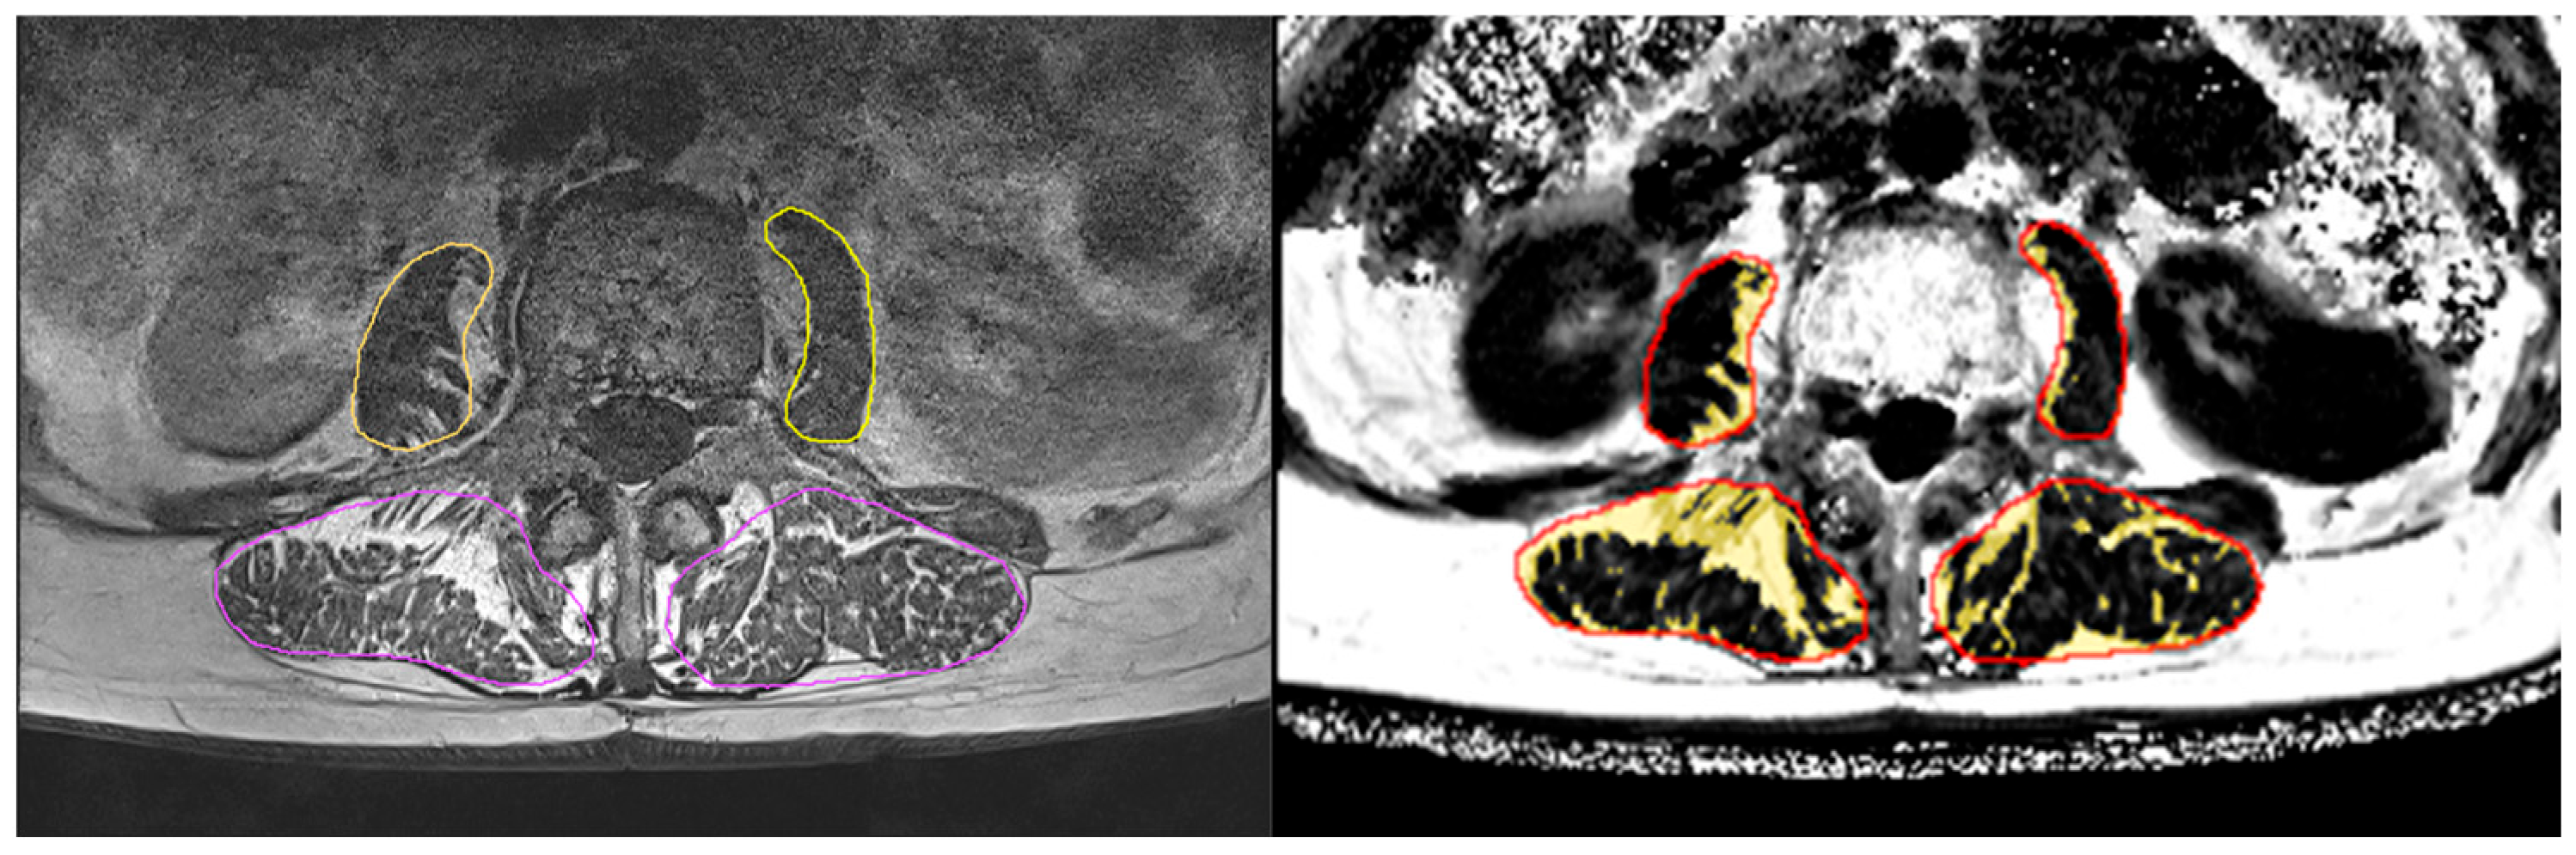

2.4.1. Magnetic Resonance Imaging (MRI)

- Chaudry, O.; Friedberger, A.; Grimm, A.; Uder, M.; Nagel, A.M.; Kemmler, W.; Engelke, K. Segmentation of the fascia lata and reproducible quantification of intermuscular adipose tissue (IMAT) of the thigh. Magn. Reson. Mater. Phys. Biol. Med. 2021, 34, 367–376. [Google Scholar] [CrossRef] [PubMed]